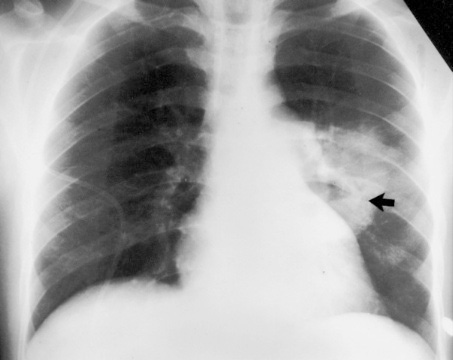

Родококкоз, как правило, встречается у лошадей и жеребят. Человек родококкозом не болеет. Но, у пациентов со СПИДом родококкоз встречается, и описано значительное количество случаев с легочными изменениями, вплоть до "кавитаций".